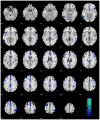

Aging is known to be associated with changes in cerebral morphometry and in regional activations during resting or cognitive challenges. Here, we investigated the effects of age on cerebral gray matter (GM) volumes and fractional amplitude of low-frequency fluctuation (fALFF) of blood oxygenation level-dependent signals in 111 healthy adults, 18-72 years of age. GM volumes were computed using voxel-based morphometry as implemented in Statistical Parametric Mapping, and fALFF maps were computed for task-residuals as described in Zhang and Li (Neuroimage 49:1911-1918, 2010) for individual participants. Across participants, a simple regression against age was performed for GM volumes and fALFF, respectively, with quantity of recent alcohol use as a covariate. At cluster level p < 0.05, corrected for family-wise error of multiple comparisons, GM volumes declined with age in prefrontal/frontal regions, bilateral insula, and left inferior parietal lobule (IPL), suggesting structural vulnerability of these areas to aging. FALFF was negatively correlated with age in the supplementary motor area (SMA), pre-SMA, anterior cingulate cortex, bilateral dorsal lateral prefrontal cortex (DLPFC), right IPL, and posterior cingulate cortex, indicating that spontaneous neural activities in these areas during cognitive performance decrease with age. Notably, these age-related changes overlapped in the prefrontal/frontal regions including the pre-SMA, SMA, and DLPFC. Furthermore, GM volumes and fALFF of the pre-SMA/SMA were negatively correlated with the stop signal reaction time, in accord with our earlier work. Together, these results describe anatomical and functional changes in prefrontal/frontal regions and how these changes are associated with declining inhibitory control during aging.